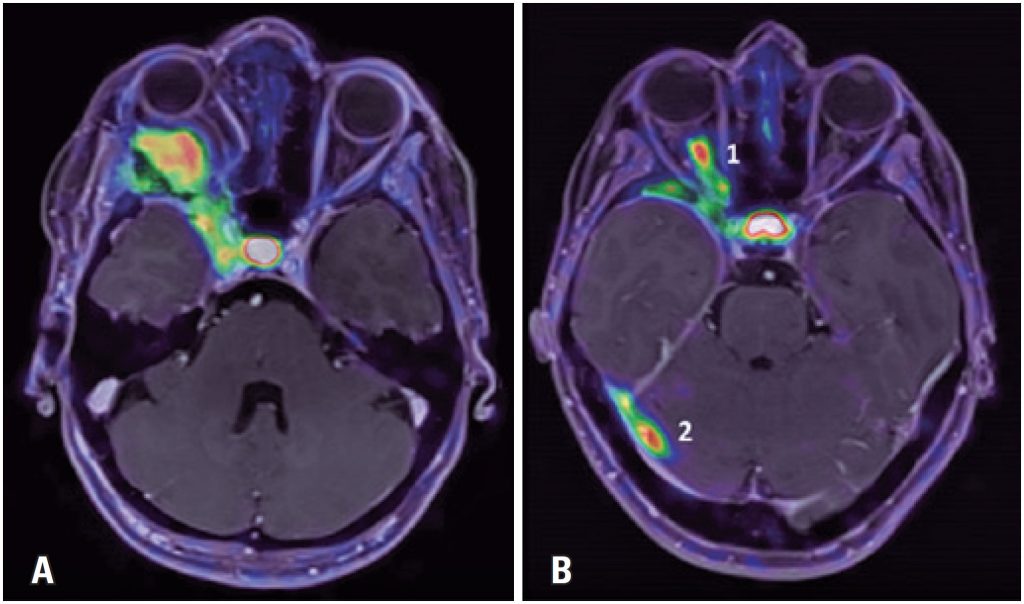

Increased uptake of radiolabeled somatostatin analogues ( a , b Radiolabeled Somatostatin Analog A somatostatin analog, dotamtate (figure 12), has been labeled with 212 pb and. Somatostatin is a neuropeptide produced by. Imaging with radiolabeled somatostatin analogues (ssas) has been integrated into the current management of nets to facilitate tumor staging and restaging and to help select patients who might benefit from radionuclide therapies [3, 4, 8]. Somatostatin receptors (ssts) are recognized as. Radiolabeled Somatostatin Analog.

Moderate uptake of radiolabeled somatostatin analogues ( a , b ; arrows Radiolabeled Somatostatin Analog Radiolabeled somatostatin analog therapy has become an established treatment method for patients with well to moderately differentiated unresectable or metastatic. Imaging with radiolabeled somatostatin analogues (ssas) has been integrated into the current management of nets to facilitate tumor staging and restaging and to help select patients who might benefit from radionuclide therapies [3, 4, 8]. Somatostatin is a neuropeptide produced. Radiolabeled Somatostatin Analog.